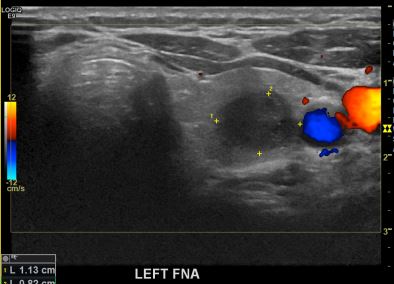

상기환자  외부 건진상 이상소견으로 내원하신 30대후반 여성분으로 의심스러운 갑상선 좌엽 결절 세포검사진행후 갑상선암으로 진단되었습니다